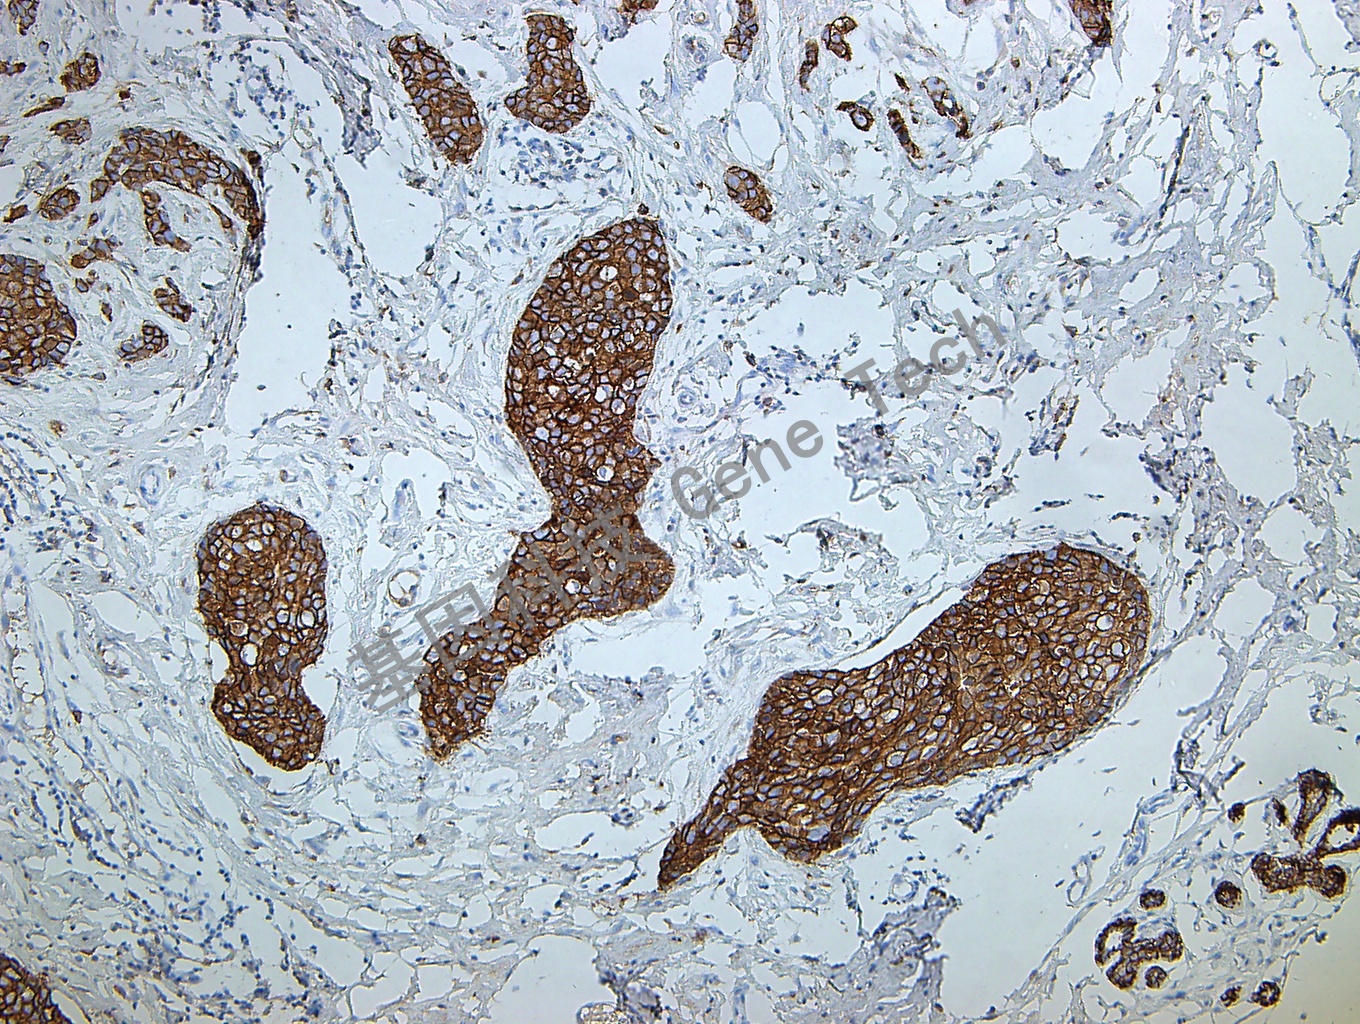

| 乳腺癌石蠟切片,用 E-Cadherin(GT2348)染色,細(xì)胞膜陽(yáng)性,DAB 顯色。 | ||

| 克隆號(hào):GM108 | 種屬:鼠 | 適用染色系統(tǒng):GTvisionTM |

| 預(yù)處理:高pH熱修復(fù) | 陽(yáng)性部位:細(xì)胞膜 | 陽(yáng)性對(duì)照:乳腺癌/結(jié)腸 |